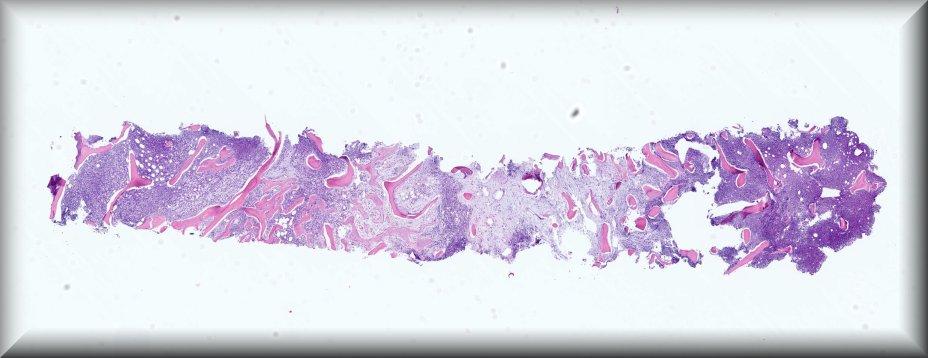

Caso 10.- Juan Díaz Nohales; Omérim Gaona Juárez; Nuria Rausell Fontestad; Javier Furriol Collado; María Soraya Hernández Girón; Empar Mayordomo Aranda.

Hospital Universitario y Politécnico La Fe. Valencia.

Paciente masculino de 82 años acude a urgencias por presencia de escalofríos y fiebre de 2 meses de evolución, con picos de hasta 39ºC. Asocia además astenia y anorexia de hasta 12 kilos durante estos meses con debilidad generalizada y alteración de la marcha, así como caídas frecuentes. En la TAC-tap se observa una esplenomegalia globulosa. Se lleva a cabo biopsia de médula ósea para estudio anatomopatológico.